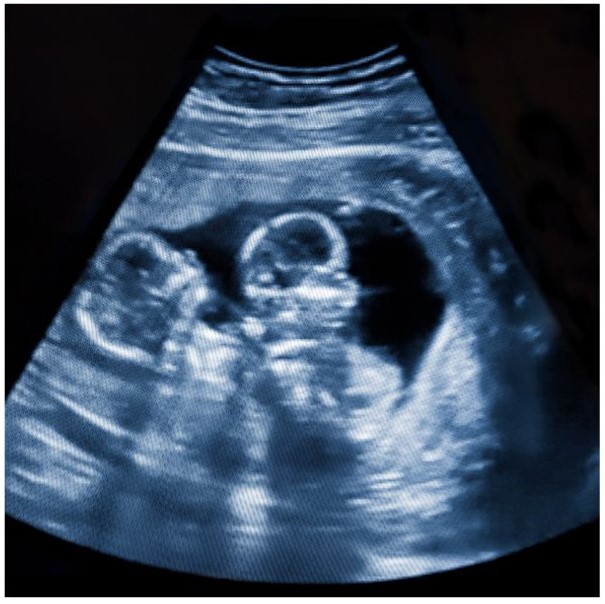

In den ersten Wochen einer Schwangerschaft kommt es sehr häufig vor, dass zwei oder mehr Embryonen im Mutterleib heranwachsen.

Moderne Ultraschalltechnologie hat gezeigt, dass bei bis zu 30 % aller Schwangerschaften zunächst Zwillinge angelegt sind – doch einer von ihnen überlebt die ersten Wochen nicht.

Der verbleibende Embryo wächst weiter, ohne dass die Mutter oder später das Kind, etwas davon weiß. Der abgestorbene Zwilling wird vom Körper resorbiert oder verbleibt in anderer Form, manchmal sogar sichtbar in der Plazenta. Manchmal taucht er Jahre später, z. B. als Zyste oder Einkapselung in Organen oder in der Wirbelsäule des Kindes, auf.